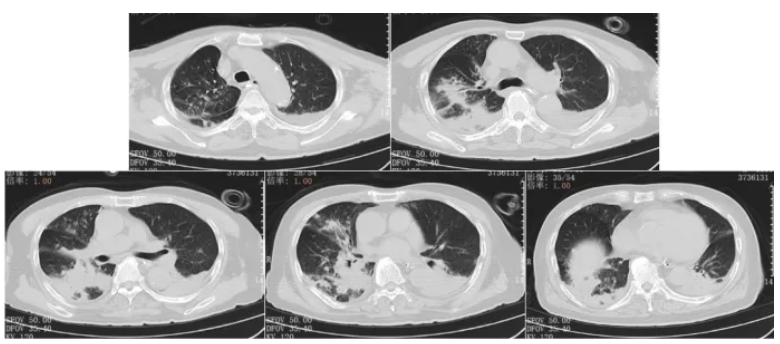

1月25日胸部CT提示双肺感染病灶较前部分吸收(图9),患者鼻导管2 L/min吸氧下,指脉氧饱和度98%,一般情况可,予以办理出院。出院带药:伏立康唑片0.2 g口服(q12h),利奈唑胺片0.4 g口服(q12h),定期门诊复查。

图9 出院前复查胸部CT(2025-01-25)